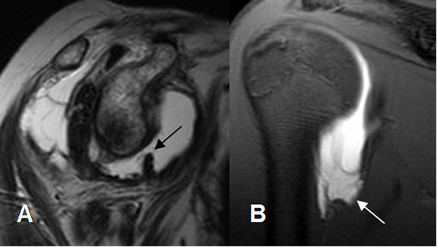

Para su diagnóstico se requiere de ArtroRM. En los cortes coronales, el receso axilar adquiere forma de “J” invertida. (Fig 78 A).

Fig 78 A. Ruptura del LGH inferior.

A: RM sagital en T2. Ruptura en la banda posterior del LGHI.

B: ArtroRM coronal en STIR. Ausencia de la banda anterior del LGHI, por ruptura.

Hay alteración en la configuración del receso axilar. (Flecha).